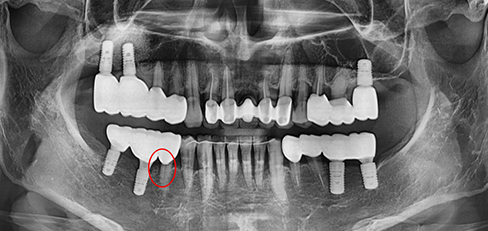

잇몸속 치아를 싸고 있는 치조골이 2/3 정도 소실되면

임플란트를 하고 그보다 치조골 손실이 적으면 비수술식

잇몸 치료를 통하여 자연치아를 최대한 살리려고 노력합니다.